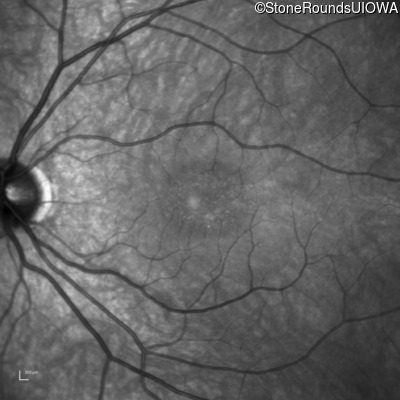

Infrared Fundus Photograph - Right - 20/16 -1

Exemplar